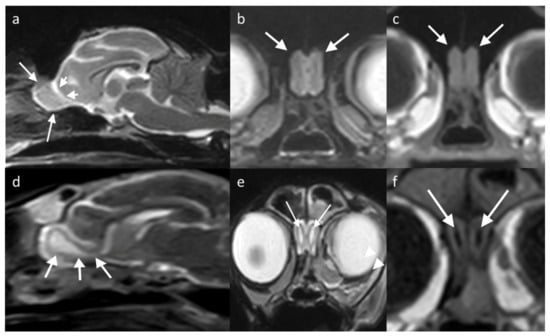

The OB in the dog can be examined in the sagittal plane, showing uniform grey matter intensity brain parenchyma resting in the olfactory fossa and circumscribed rostrally by the cribriform plate. The olfactory fissure separates it from the rest of the brain with a thin band of CSF (hyperintense on T2W, hypointense on T1W) [29]. The bulb has a different orientation in different skull conformations, lying rostral to the frontal lobe in mesaticephalic or dolicocephalic breeds, and ventral to it in brachycephalic breeds (Figure 5).

Figure 5. MRI brain of two dogs with different conformation, showing the location of the OBs (white arrows show the rostral extent, bounded by the lamina cribrosa (cribriform plate)). (a,d) T2W sagittal/slightly parasagittal to line through with the OB, with white arrowheads highlighting the olfactory fissure which separates the OB from the frontal lobe; (b,e) T2W transverse at the level of the OB; and (c,f) T1W transverse equivalent. (ac) are of a brachycephalic breed (6-year-old French Bulldog) showing that the OBs are located on the rostroventral aspect of the brain; therefore, are seen ventral to the frontal lobes on the transverse view. (df) is a mesocephalic breed (12-year-old Golden retriever) with the OBs protruding from the rostral aspect of the brain. Transverse slices from patients with this conformation therefore show only the OBs and small segments of the surrounding brain.